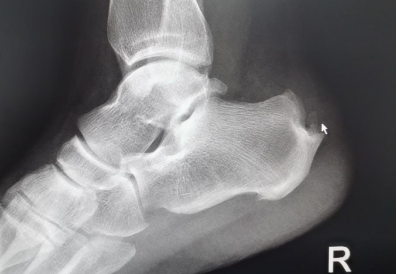

“經(jīng)X光、磁共振等詳細(xì)檢查,提示患者雙側(cè)跟骨結(jié)節(jié)增生、跟腱有變性,雙側(cè)跟骨結(jié)節(jié)區(qū)域及跟腱止點(diǎn)表現(xiàn):組織充血、水腫,結(jié)合病情及查體,考慮跟骨骨性突起畸形,經(jīng)診斷,為Haglund綜合癥(止點(diǎn)性跟腱炎、跟骨后上突增生與跟腱滑囊炎的統(tǒng)稱)?!崩畋蛑魅伪硎荆摬“Y主要表現(xiàn)為跟腱止點(diǎn)部位疼痛不適,運(yùn)動時疼痛加劇;或者清晨起床后出現(xiàn)疼痛,漸進(jìn)性病程發(fā)展,后期疼痛加重,影響生活質(zhì)量。

考慮患者術(shù)后行動問題,8月18日,在李彬主任的帶領(lǐng)下,手術(shù)團(tuán)隊(duì)首先為其治療疼痛更甚的右腳。術(shù)中,僅開了兩個很小(直徑5毫米左右)的口子,在關(guān)節(jié)鏡下磨除右側(cè)跟骨后增生骨質(zhì),去除骨撞擊,清理炎性組織,手術(shù)順利完成。